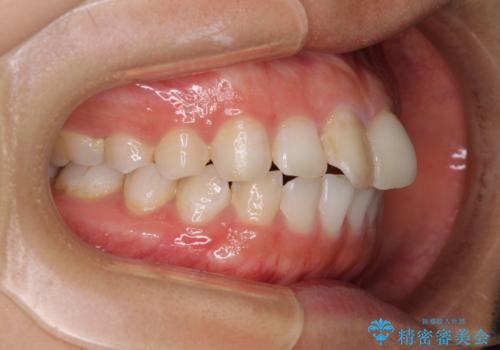

前歯の捻れを改善 インビザラインによる矯正治療

- 前歯の翼状捻転を気にして来院された患者様です。

全体的に叢生は軽度であったため、インビザラインにて矯正治療を行うこととしました。

前歯の幅の大きさも気になっていたため、IPRにより叢生を解消するとともに、歯の大きさも改善しました。